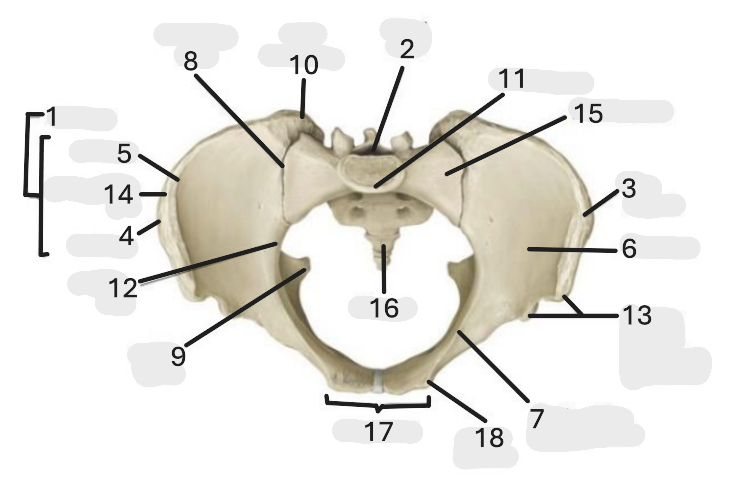

Where is the pelvic inlet

1

Where is the sacro-iliac joint

2

Where is the pubic tubercle

3

Where are the S1 body

4

Where is the ischial spine

5

Where is the ala of sacrum

6

Where is the anterior superior iliac spine

7

Where is the ischiopubic ramus

8

Where is the coccyx

9

Where is the obturator foramen

10

Where is the pubic symphysis

11

Where is the ischial tuberosity

12